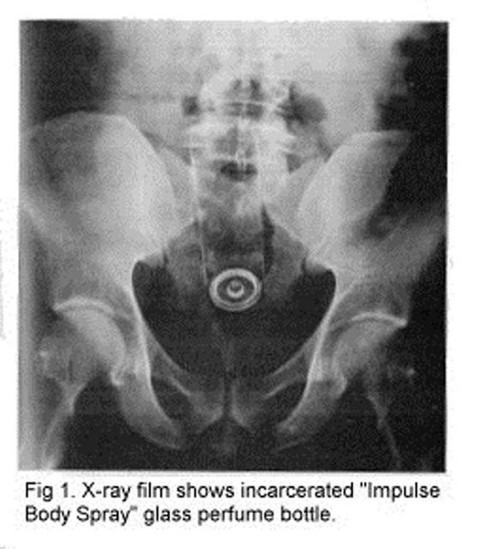

Galerinin tamamı için tıklayınızPARFÜM ŞİŞESİ; Anüsünde parfüm şişesinin sıkıştığını söyleyen 39 yaşındaki adam acil servise başvurdu. Daha önce de aynı işlemi yaptığını fakat sorun yaşamadığını söyleyen adam bu sefer sıkışıp kaldığını belirtti.